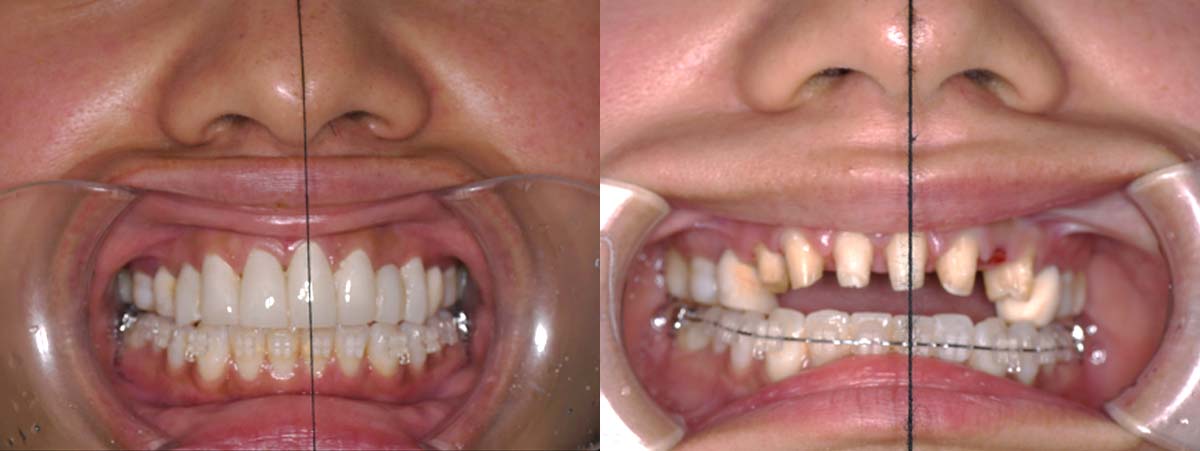

2024年 10月 下顎MTM開始

姿勢の変化

2024年 3月 初診時

2024年 10月10日

2025年 12月25日

顔貌の変化